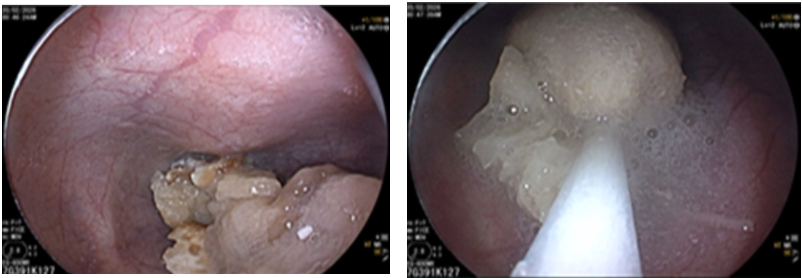

🌿 Người phụ nữ 74 tuổi: Nghẹn măng sau mâm cỗ

Bà V.T.N (74 tuổi, Hà Nội) xuất hiện nuốt nghẹn sau khi ăn măng trong mâm cỗ Tết. Nghĩ chỉ là nghẹn tạm thời, bà thử nhiều cách dân gian như uống nước thật nhiều, nuốt cơm to, ăn thêm rau… nhưng không đỡ.

Nội soi dạ dày cho thấy thức ăn mắc lại trong thực quản. Dị vật được lấy ra kịp thời.

Ở người cao tuổi, phản xạ nuốt giảm, răng yếu, khả năng nhai kém. Những thực phẩm dai và nhiều xơ như măng, thịt bò, thịt gà rất dễ gây nghẹn nếu không được cắt nhỏ và nhai kỹ.